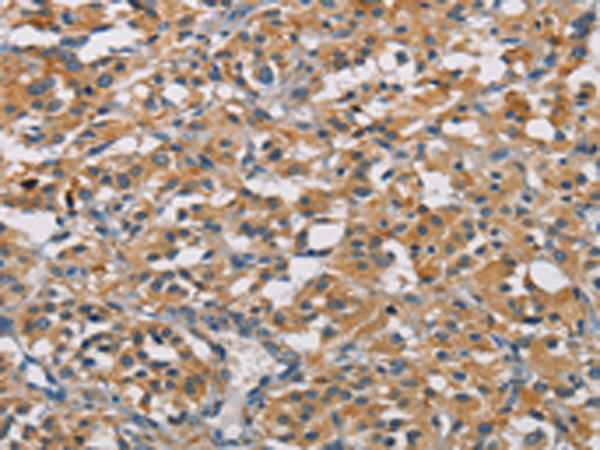

分类: 科研抗体货号: P07997别名: DFNB98; TSP-EAR; C21orf29应用: IHC反应种属: Human